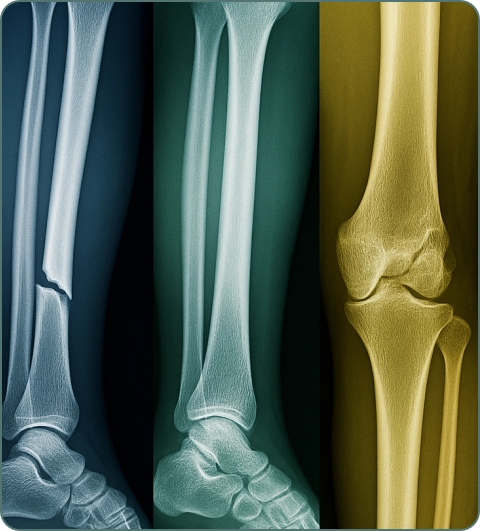

Fractures and Trauma

Broken bones due to accidents, falls, or sports injuries. Can be simple or complex, requiring casting, surgery, or external fixation for proper healing.

X-rays

First-line imaging for fractures, joint problems, and bone abnormalities. Quick, cost-effective, and excellent for detecting bone fractures and arthritis.

Cross-sectional imaging for complex fractures, bone tumors, and detailed joint anatomy. Useful for surgical planning and trauma assessment.